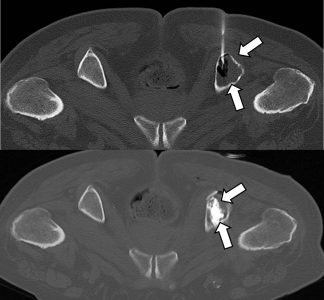

Σε έναν δεύτερο πυλώνα ογκολογικής θεραπείας η Επεμβατική Ακτινολογία μπορεί να εφαρμόσει τοπικοπεριοχική θεραπεία καταστροφής των καρκινικών κυττάρων με τεχνικές είτε διαδερμικής κατάλυσης (Ablation) είτε διαδερμικού ενδαγγειακού χημειοεμβολισμού (TACE). Στην περίπτωση της κατάλυσης μπορεί να εφαρμοστεί σε καρκινώματα του ήπατος, του νεφρού, των οστών και των όγκων μαλακών μορίων και υπό προυποθέσεις στον πνεύμονα. Παθοφυσιολογικά βασίζεται στην τοπική καταστροφή των καρκινικών κυττάρων με τη δημιουργία ιδιαίτερα υψηλών θερμοκρασιών νέκρωσης εντός του όγκου. Αυτό επιτυγχάνεται με τοποθέτηση ειδικών βελονών-ηλεκτροδίων εντός του όγκου υπό ακτινολογική καθοδήγηση. Τα ηλεκτρόδια αυτά παράγουν υψηλή θερμοκρασία είτε με τη βοήθεια ραδιοσυχνοτήτων (RF ablation) είτε με τη βοήθεια μικροκυμάτων (MW ablation) και προκαλούν πηκτική νέκρωση των καρκινικών κυττάρων χωρίς να επηρεάζουν τα φυσιολογικά κύτταρα.